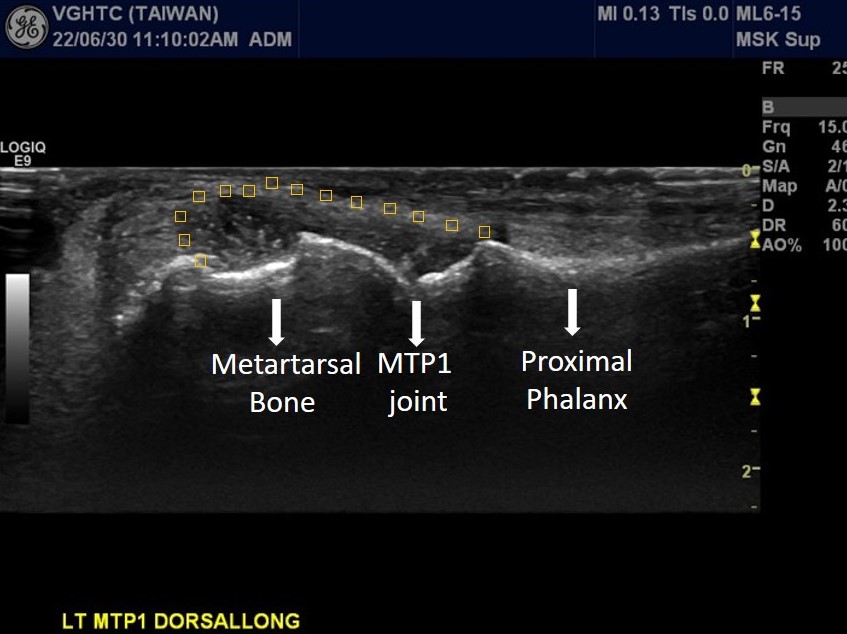

Longitudinal scan at suprapetellar region of right knee with power Doppler ultrasound showed increased joint effusion (asterisks in Picuture 6 ). Posterior longitudinal scan of right elbow with power Doppler ultrasound showed increased joint effusion at olecranon fossa (asterisks in Picutre 7) with hypervascularity (red color signal), indicating active arthritis of right elbow. Dorsal longitudinal scan at left MTP1 showed synovial hypertrophy with heterogeneous echogenicity , possible crystal deposition. (Picuture 8). Dorsal longitudinal scan with power Doppler ultrasound at right MCP3 showed synovial hypertrophy with hypervascularity (red color signal in Picture 9), indicating active arthritis.

Picuture8. Lt MTP1